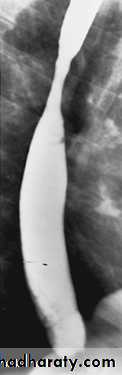

Peptic stricture

Found in the lower end of esophagus , almost invariably associated with a hiatus hernia and gastro-esophageal reflux. Peptic strictures are characteristically short and have smooth outlines with tapering ends. Ulcer may be seen nearby.